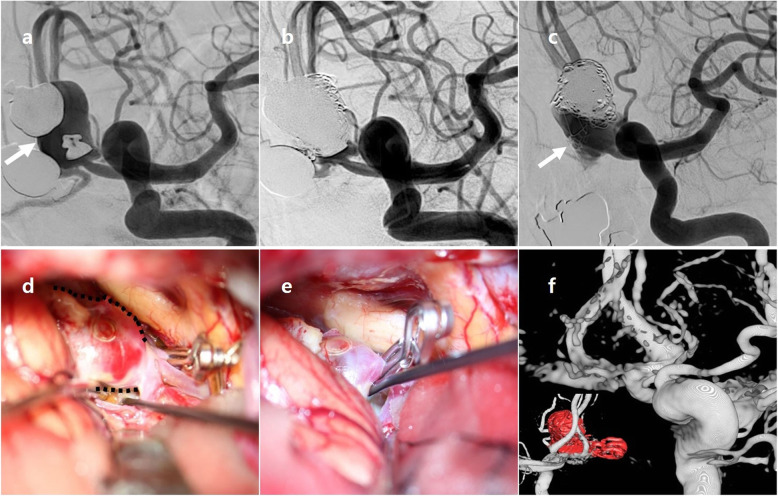

A 55-year-old female patient underwent an emergency CT scan due to mental change. Ruptured Acom aneurysm was noted. Maximal size of aneurysm was 16.6 mm and neck size 6.6 mm. Emergent EVT was performed and immediate post-embolization angiogram showed neck remnant occlusion (class II). Patient recovered well and she was discharged without neurological deficit. After 1 year, cerebral angiography revealed a recurrence of aneurysm (class III). Surgical clipping was done without neck remnant, and both A2 segments were safely preserved. No more recurrence was seen after 2 years. These findings are described in Fig. 1.

A 55-year-old patient with recurrent Acom aneurysm. Initial angiogram (a) showed a ruptured Acom aneurysm (arrow); maximal height 16.6 mm, neck size 6.6 mm. Immediate post-embolization image (b) showed a neck remnant (class II) occlusion of aneurysm without distal sac flow. After one year, cerebral angiography (c) revealed a recurrence of aneurysm (arrow, class III). Intraoperative image (d) showed recurrent aneurysm sac (dotted line), and temporary clipping was applied for exploration of aneurysm sac. Permanent clipping was done, and there was no remnant sac (e). On post-operative 3D reconstructive image (f), no remnant sac was noted. Acom = anterior communicating artery